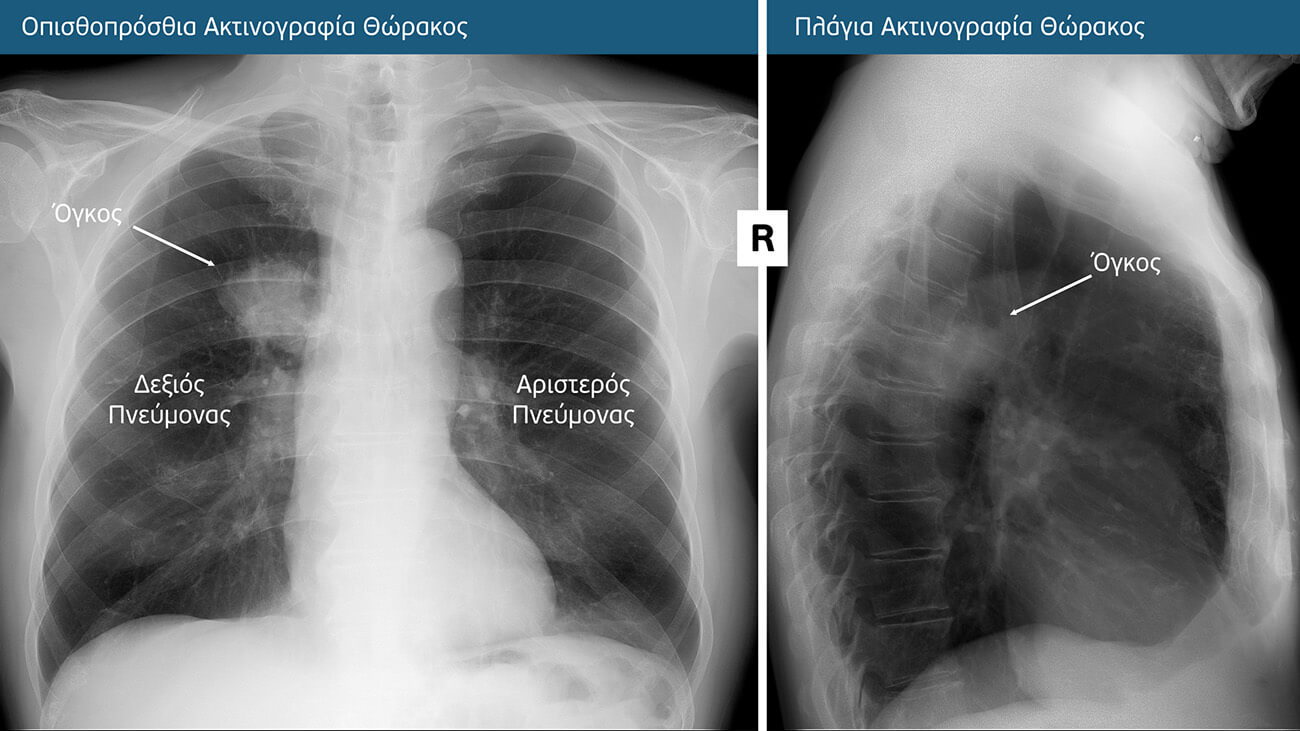

Ακτινογραφία Θώρακος

Η ακτινογραφία θώρακος αποτυπώνει εικόνες όλων των δομών του θώρακα (οστών, πνευμόνων, καρδιάς, αγγείων, σπονδυλικής στήλης κλπ).

Η ακτινογραφία θώρακος είναι η απλούστερη και συχνά η πρώτη εξέταση που διενεργείται για την ανίχνευση πνευμονικών αλλοιώσεων ή όγκων, όταν υπάρχουν γενικευμένα συμπτώματα. Μπορεί επίσης κατά τύχη να αποκαλύψει πνευμονικούς όγκους ενώ διενεργείται για άσχετη αιτία. Ωστόσο, όταν η νόσος βρίσκεται στο αρχικό της στάδιο, οι ακτινογραφίες θώρακος συχνά είναι ανεπαρκείς και δεν είναι σε θέση να εντοπίσουν μικρούς καρκινικούς όζους στον πνεύμονα και γι’ αυτό όταν υπάρχει ανησυχία για καρκίνο του πνεύμονα, πρέπει ο ασθενής να υποβάλλεται σε αξονική (υπολογιστική) τομογραφία θώρακος.